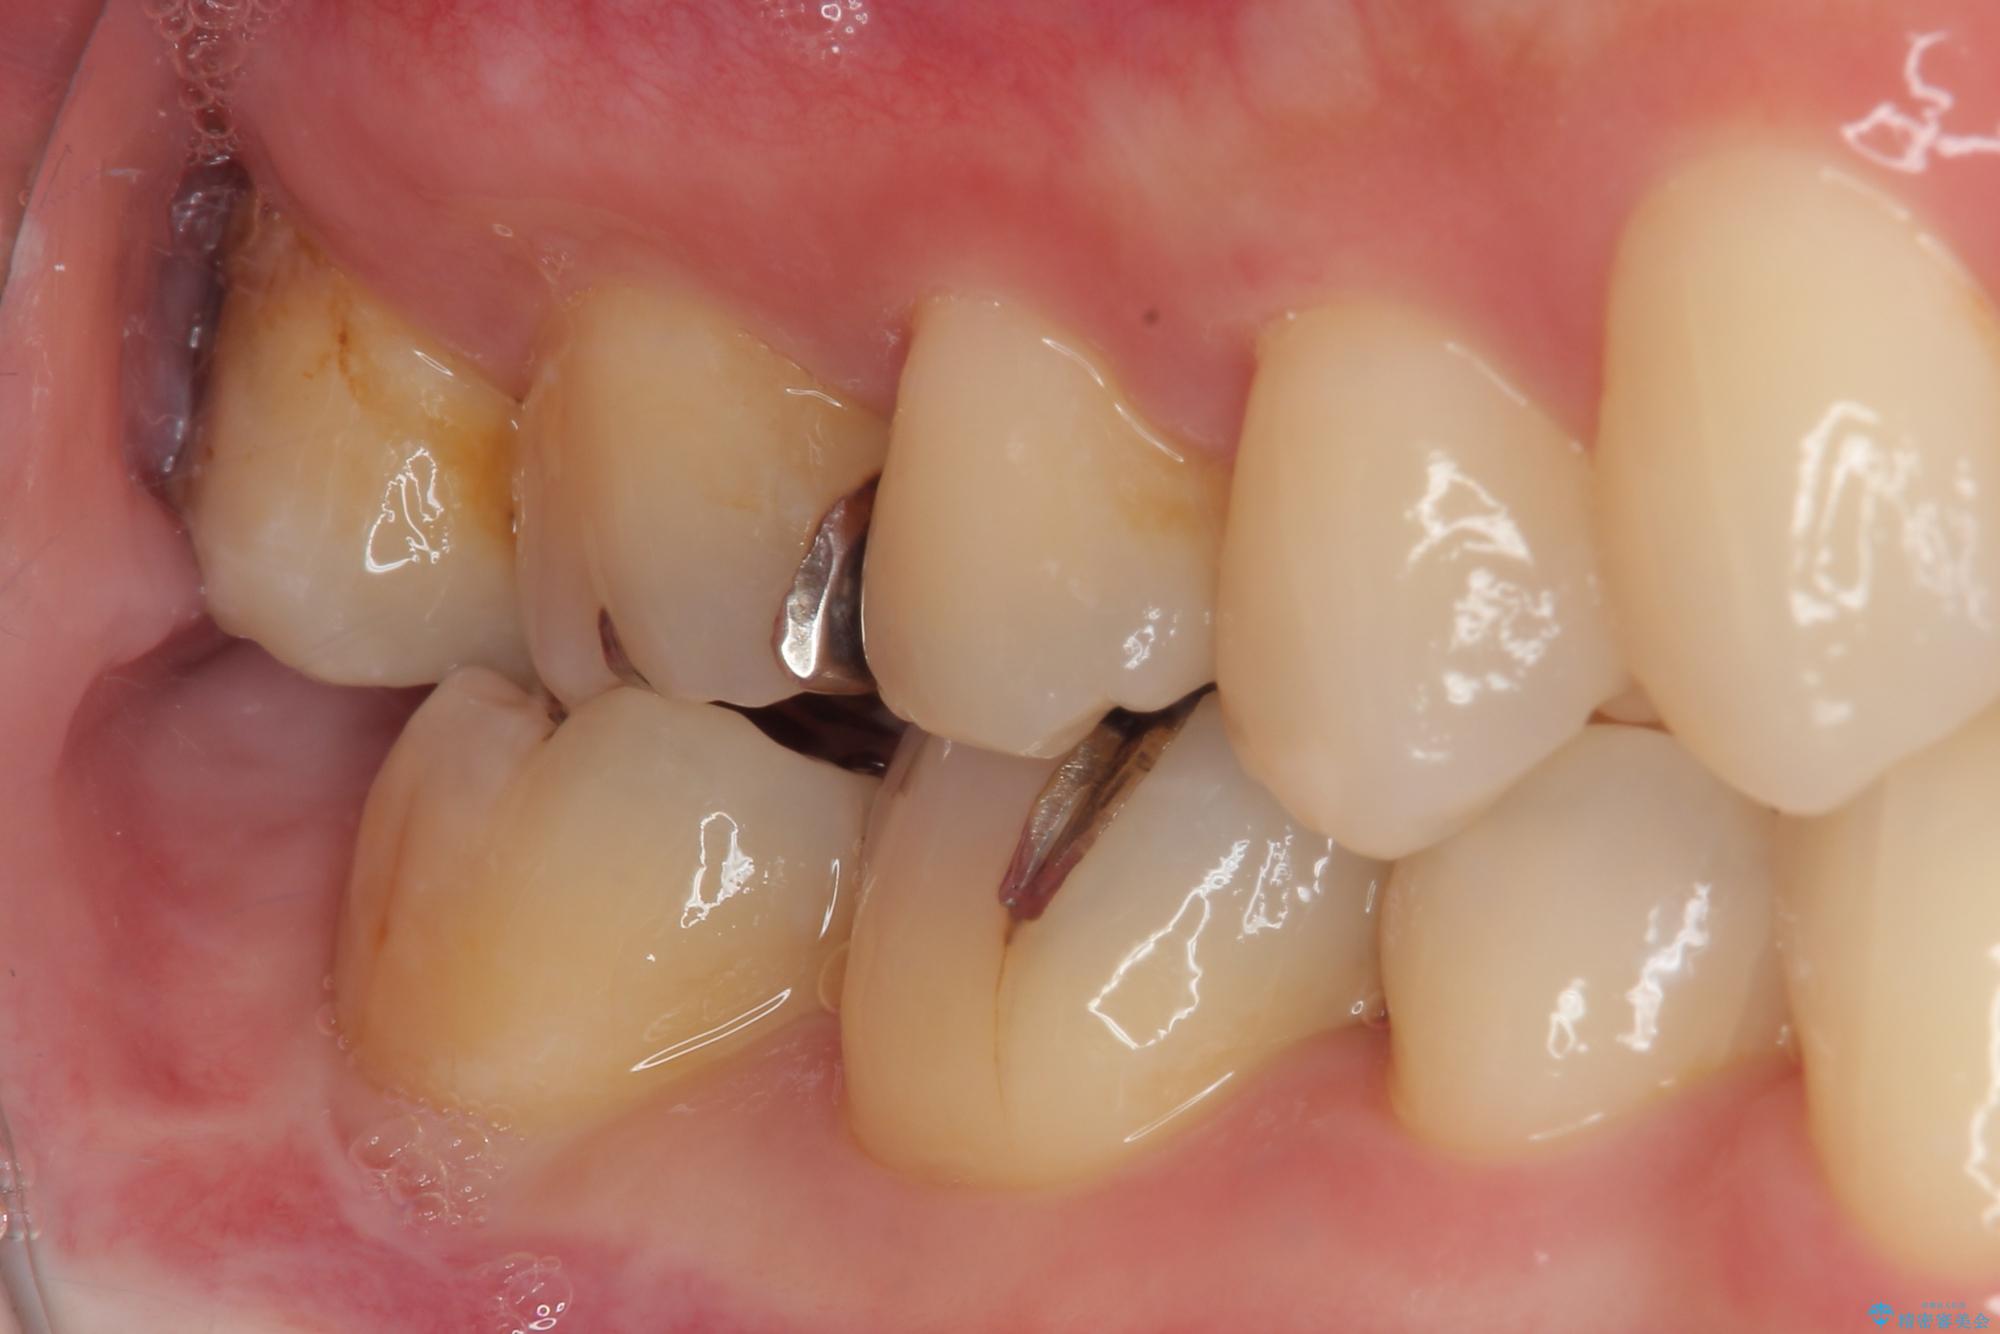

- 元々むし歯があったものの、処置が困難とのことでしたが、矯正治療を終えたので処置をしたいとのことで来院された患者様です。

左右ともに最後臼歯が頬側に顕著に突出しており、むし歯になってしまったことが想像されました。

矯正治療により処置が可能な位置に歯が移動したため、オールセラミッククラウンにて補綴治療を行うこととしました。

歯列が移動したとはいえ、左右ともに後方傾斜しており、むし歯の除去、形成(形を整える)、型取りの全てが非常に困難な処置となりました。